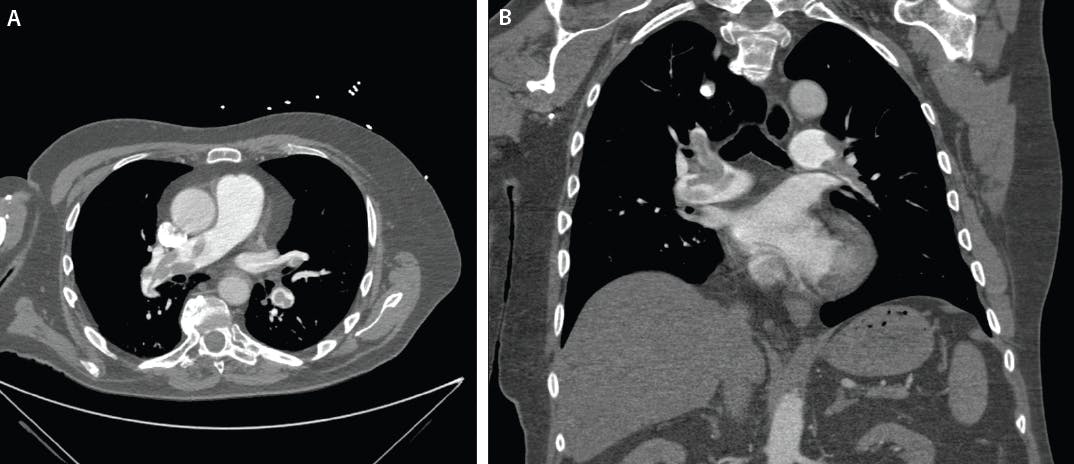

Laboratory evaluation showed elevated D-dimer (4.8 µg/mL) and mildly increased troponin I. CT pulmonary angiography (CTPA) demonstrated a saddle PE extending into both main pulmonary arteries (PAs) (Figure 1). Echocardiography revealed marked RV dilation with a RV/LV (right ventricular/left ventricular) ratio of 1.4, consistent with RV strain (Figure 2).

Figure 1. Transverse plane CTPA demonstrating a saddle PE extending into both main PAs (A). Coronal plane CTPA demonstrating a saddle PE extending into both main PAs (B).